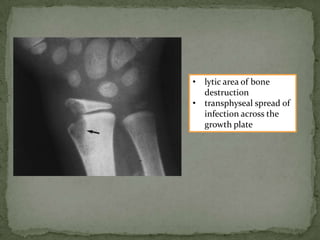

• lytic area of bone

destruction

• transphyseal spread of

infection across the

growth plate

T2 fat sat